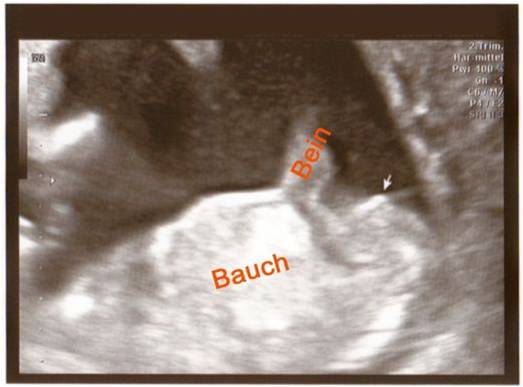

Hello Everyone! Its me again :-) A Gender swaying friend (wanting a Girl) made the The Baby Gender Predictor Test: Am I having a boy or girl? DNA - Test And it said -> BOY! Her second son is 19 Months old and she was pretty careful making the test... Now she went to her doctor’s appointment and the doctor was sure it’s a Girl!! What do you think? Picture 1 : (NT-Scan – Baby Nr.3 -> Is the current pregnancy ) Sohnemann 2 is her second Boy ;-) Picture 2: 17 weeks pregnant potty scan the arrow should show the girl parts .... So Ladys what do you think any chance itīs a GIRL??? Greetings & Thanks ....

Attachment 10346

Bauch= Belly

Bein = Leg

-> = Gender